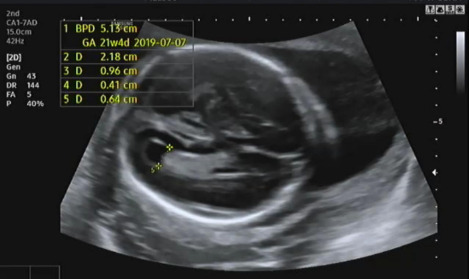

그다음 태아의 머리 둘레를 측정하고 21주 차에 맞게 뇌가 주수에 알맞게 발달하였는지, 물혹 등의 여부나 기형이 있는지 확인을 한다.